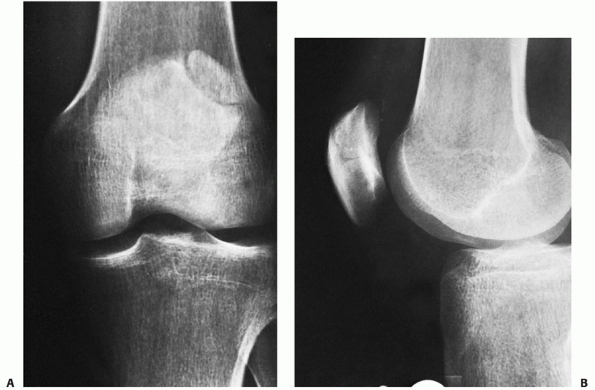

diagnosis of patellar fracture or injury to the extensor mechanism.

Anteroposterior (AP), lateral, and a tangential or axial view of the

patellofemoral joint should be obtained (Fig. 52-1).

FIGURE 52-1 Anteroposterior (A), lateral (B), and axial (C) views of a displaced transverse patella fracture.